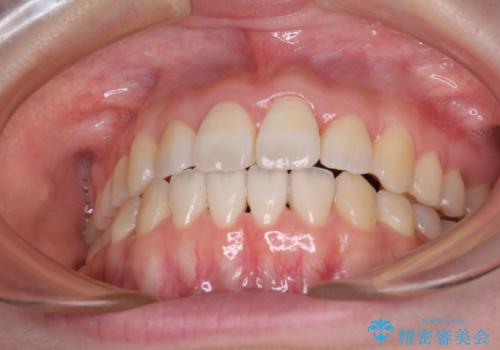

- 前歯の捻れと、ちょっとした出っ張りを気にして来院された患者様です。

歯と歯の間を削る(IPR)ことでデコボコを解消し、インビザラインで整えることとしました。

インビザライン治療特有の奥歯が接触しない時期が続き、当初予定よりも期間がかかりましたが、最終的には安定した咬み合わせと、整った前歯になりました。